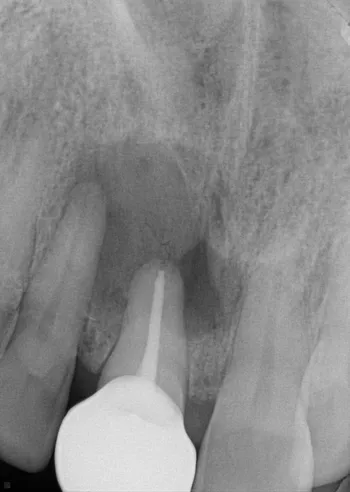

Before

After

Patient is a 64 year old female. Recommended treatment for root canal on teeth 7 and 9 and retreatment of 10. The first x-ray is dated 6-23-23, procedure was completed 7-7-23. She was seen for 6 months follow up visit 1-10-24 and has had some tenderness and swelling recommended CBCT for comparison. Dr. Malavia did recommend Apicoetomy for teeth #9 and 10, surgery was done 2-20-24. The final x-ray is dated 3-7-25